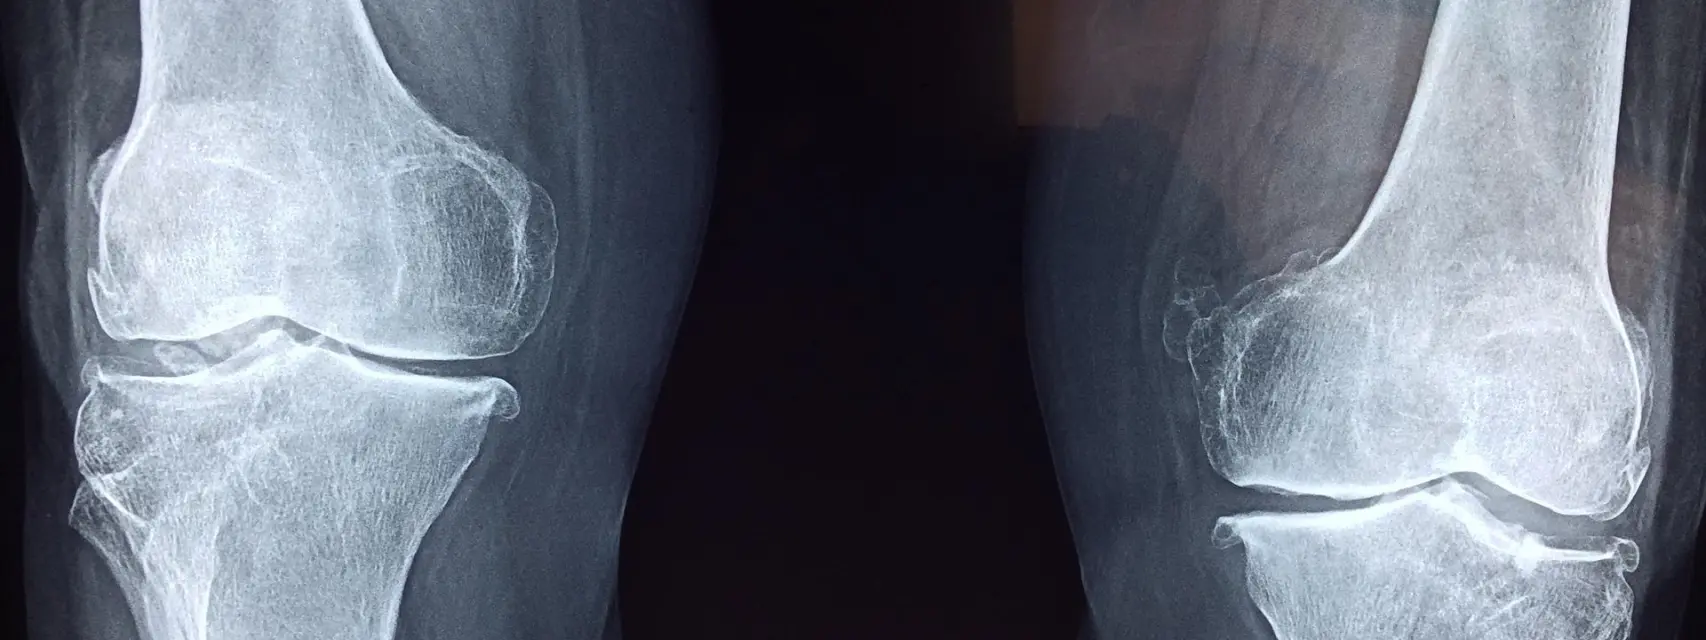

La exposición temprana a sustancias perfluoroalquiladas y polifluoroalquiladas (PFAS), que son muy persistentes, puede influir en el desarrollo óseo de los niños durante la adolescencia, según una nueva investigación publicada en el «Journal of the Endocrine Society».

Los autores estudiaron las concentraciones sanguíneas de PFAS de 218 adolescentes de una cohorte prospectiva de embarazo y nacimiento al momento del parto y a los 3, 8 y 12 años de edad. Midieron la densidad ósea a los 12 años y encontraron que los adolescentes con niveles más altos de ácido perfluorooctanoico (PFOA) en sangre tenían menor densidad ósea en el antebrazo.